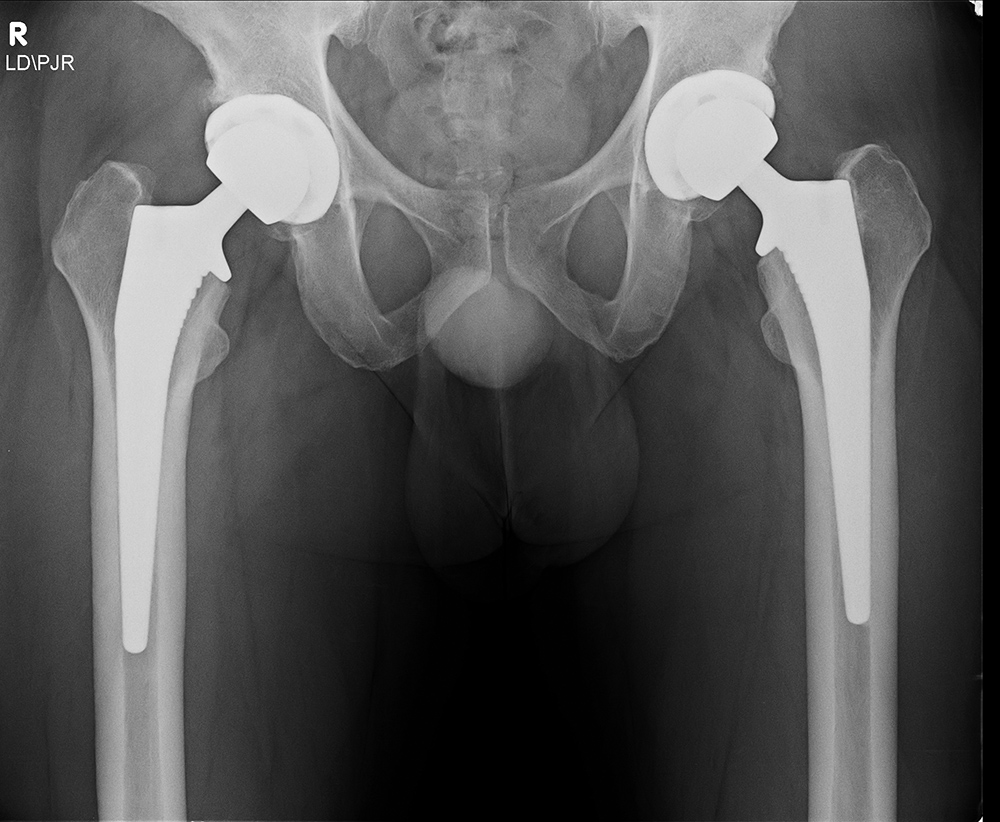

Bilateral total hip replacement is a procedure where both hip joints are replaced with prosthetic implants. This involves removing the damaged cartilage and bone in each hip, reshaping the socket (acetabulum), and inserting a prosthetic cup and stem into the pelvis and femur.

The surgical goal is to recreate healthy joint movement on both sides, restore your leg length balance, and improve overall function. The procedure may be performed either during the same operation (simultaneous) or as two separate surgeries (staged).